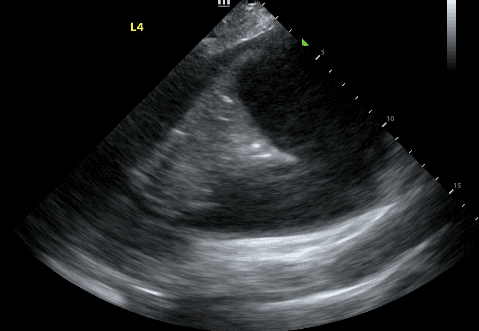

If a pleural effusion is present, there will be an anechoic (ie. black) space above the diaphragm. Please note that an anechoic space below the diaphragm represents ascites; not a pleural effusion. Two other other features will stand out to you. Firstly, you will see a “spine sign.” Normally, the spine cannot be visualized above the diaphragm since aerated lung scatters ultrasound beams before it can reach the spine. However, a pleural effusion will allow sound waves to be transmitted to the spine and you will see the spine clearly visible above the diaphragm.

Secondly, you will see a consolidated lung sitting in the effusion. Please refer to our post on consolidations to learn what consolidated lung looks like. If the effusion is large, the consolidated lung will appear to float in the effusion - resembling a jellyfish swimming in the ocean. This is referred to as the “jellyfish sign.”